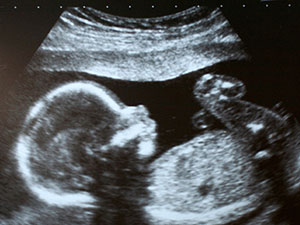

usb 24 hepdeМай: Это девочка!

Количество тестов за этот месяц: 3

Количество врачей: 2

Сколько в среднем была в очереди: 1 час

Заплатила в кассу: 220 манат

Количество УЗИ: 1

19-23 неделя беременности наверное, станут самыми любимыми неделями будующих мам и тех, кто готовится к беременности. Живот еще не слишком большой, но вы уже чувствуете себя полностью беременной. Появляются первые шевеления ребенка. Вы можете увидеть пол ребенка, а угроза выкидыша очень низкая. Я не сразу поняла, что чувствую именно шевеления, а муж так и вовсе почувствовал легкие движения только через пару недель. Потом муж регулярно прикладывал руки и уши, чтобы почувствовать, как двигается ребенок.